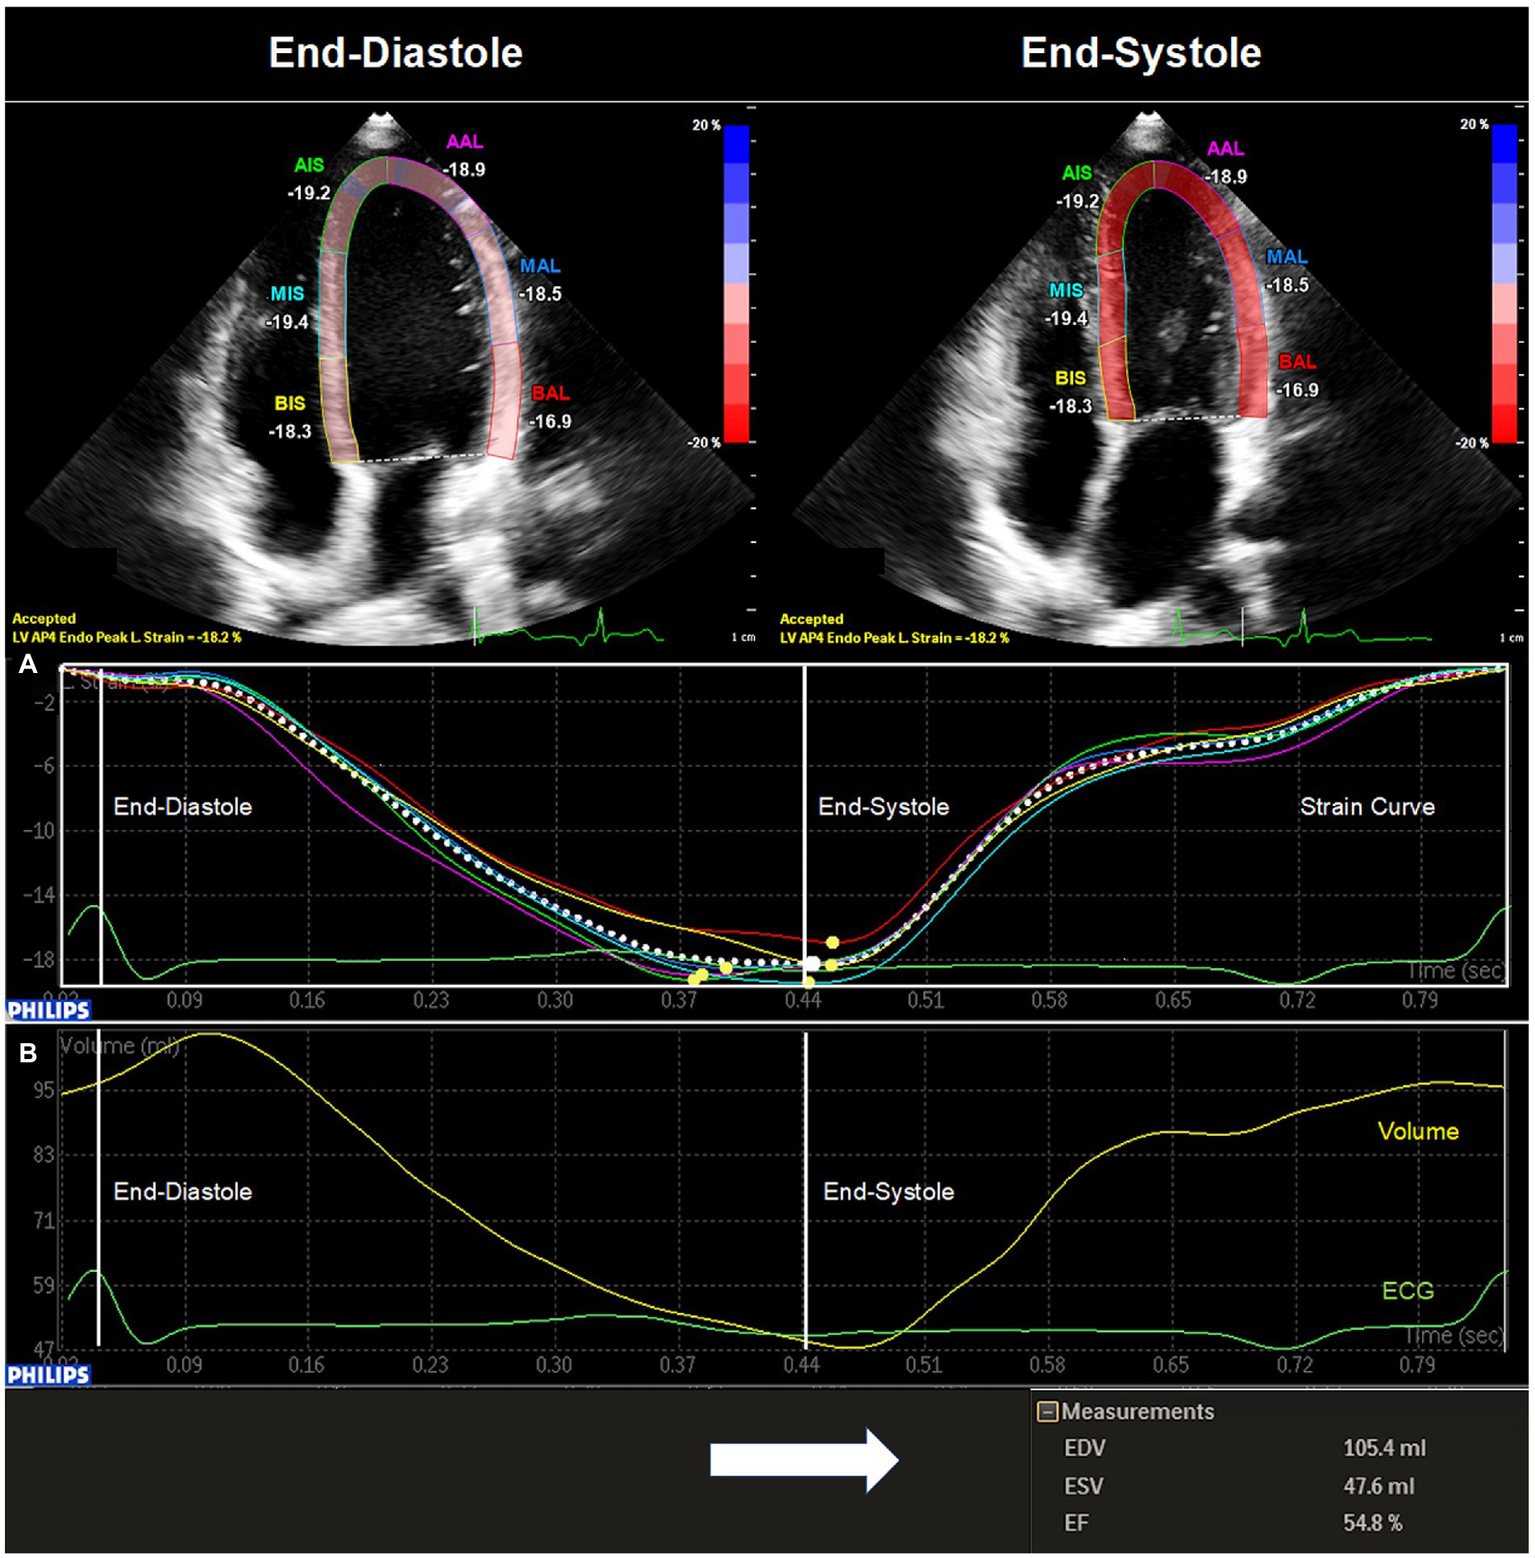

Images for 2DSTE were acquired in apical two chamber view (A2C), apical three chamber view (A3C) and A4C. In each chamber view, four loops were recorded under constant ECG tracking. Recordings were then transferred to an offline workstation (QLAB cardiovascular ultrasound quantification software, version 11.1, Philips Healthcare, The Netherlands) for further analysis. In end-diastole the investigator marked the endocardium at three fixed points. The endocardium was then automatically marked at end-diastole by the software. Myocardial speckles of the LV were then tracked by the software throughout the cardiac cycle until end-systole allowing the calculation of peak longitudinal strain for each chamber view. The investigator could manually adjust the region of interest at end-diastole and at end-systole if necessary. Global peak longitudinal strain (GPLS, %) was assessed for A2C (GPLS_A2C, %), A3C (GPLS_A3C, %), and A4C (GPLS_A4C, %) (Figure 1A). Moreover, an average of the above-mentioned values was calculated (GPLS_AVG, %). Additionally, EDV, ESV and EF were assessed semiautomatically by the software (QLAB cardiovascular ultrasound quantification software, version 11.1, Philips Healthcare, The Netherlands) in A4C (Figure 1B).

Figure 1

Two-dimensional speckle tracking echocardiography of the left ventricle. The image was acquired through echocardiography in apical four chamber view and transferred to an offline workstation (QLAB cardiovascular ultrasound quantification software, version 11.1, Philips Healthcare, The Netherlands) for further analysis. In end-diastole (QRS in ECG) the investigator marked the endocardium at three fixed points. The endocardium was then automatically marked at end-diastole by the software. The investigator could manually adjust the region of interest at end-diastole and at end-systole (end of T-wave in ECG) if necessary. (A) Global peak longitudinal strain for apical four chamber view (GPLS_A4C, %) was then automatically assessed by the software at end-systole. (B) In addition, a left ventricular volume curve was generated enabling the calculation of left ventricular end-diastolic volume (EDV, mL), left ventricular end-systolic volume (ESV, mL), and left ventricular ejection fraction (EF, %).